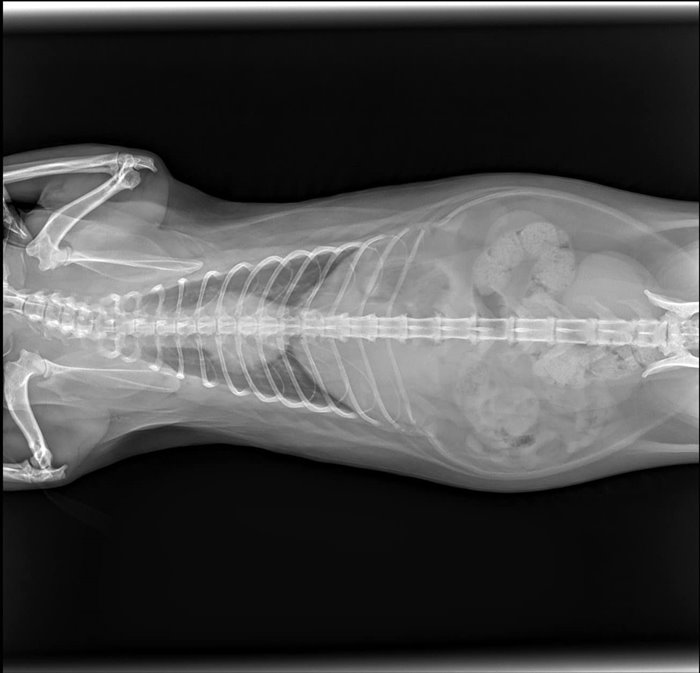

วันที่ 28 พฤษภาคม 2566 สรยุทธ สุทัศนะจินดา รายงานว่า ได้มีการอัปเดตอาการ น้องซิฟู เหมียวน้อยตัวดังกล่าวว่า "อัปเดตอาการน้องซิฟู หรืออาจารย์ซิฟู ในกังฟูแพนด้านั่นเอง น้องปกติทุกอย่าง กินข้าวได้ อึขับถ่ายปกติ ไม่มีอาการบวมหรือช้ำในใด ๆ มีเพียงแค่เล็บหลุด 2 นิ้ว และเป็นห้อเลือดเท่านั้นครับ"